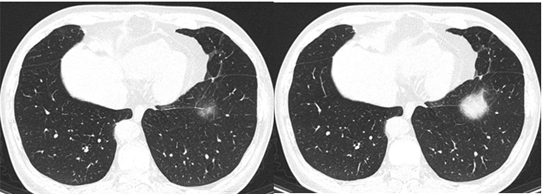

肺部感染经典影像征象

ct31147:肺水肿心功不全合并肺感染

肺部感染 ct 太难学?看完这篇不信你还不会!

肺部感染ct读片,这6个坑你一定踩过

肺部感染ct图片

严重肺部感染ct图片

肺部感染ct图片怎么看

肺部感染的ct影像图片

肺部感染ct